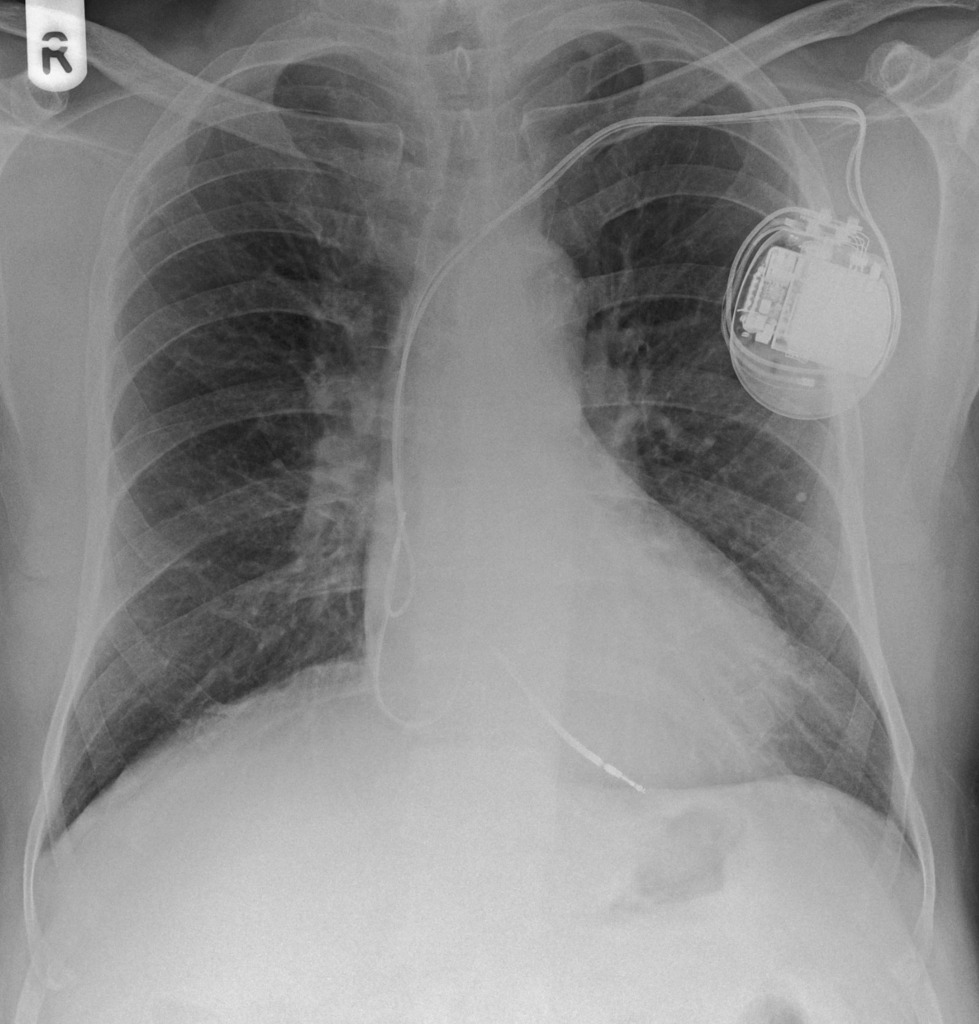

“On initial inspection, there appears to be a foreign object in the upper left chest, but I will proceed to go through it systematically.”

A – Starting with the airways, the trachea is not deviated, and the carina is visible.

B – The pleural markings go all the way to the costal margin so there is no evidence of a pneumothorax. Going through the lung zones, there is no opacification.

C – The heart is not enlarged and there is no loss of the heart border.

D – The hemidiaphragms are clearly visible and there is no blunting of the costophrenic angles. There is no free air under the diaphragm.

E – There is a pacemaker present, situated under the left clavicle. There are 2 wires which attach to the right atrium and the left ventricle.

There is no abnormality in the review areas, including the apices, behind the heart.

In summary the key finding is that there’s a pacemaker in situ

Pacemaker